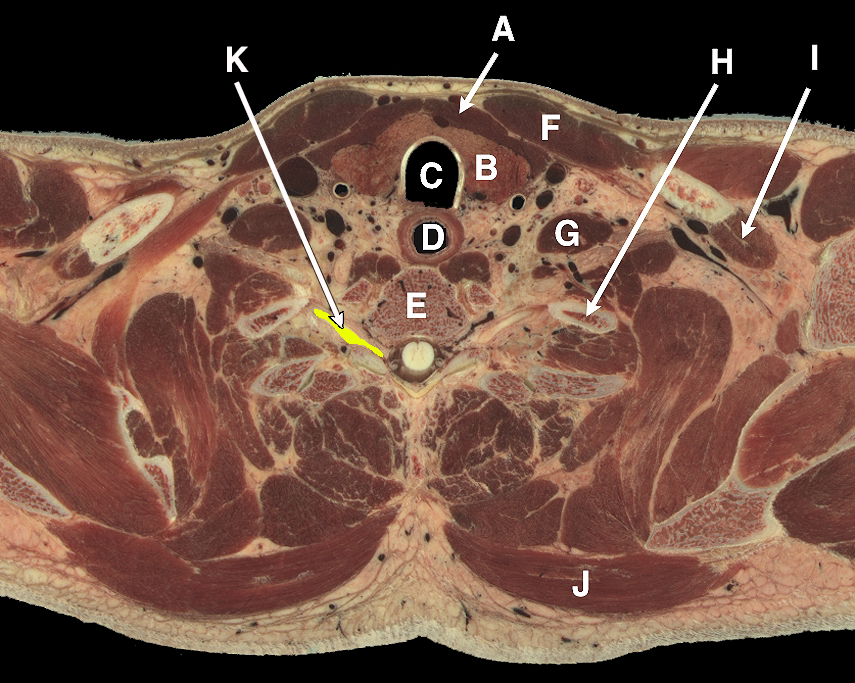

• Neck structures, high resolution